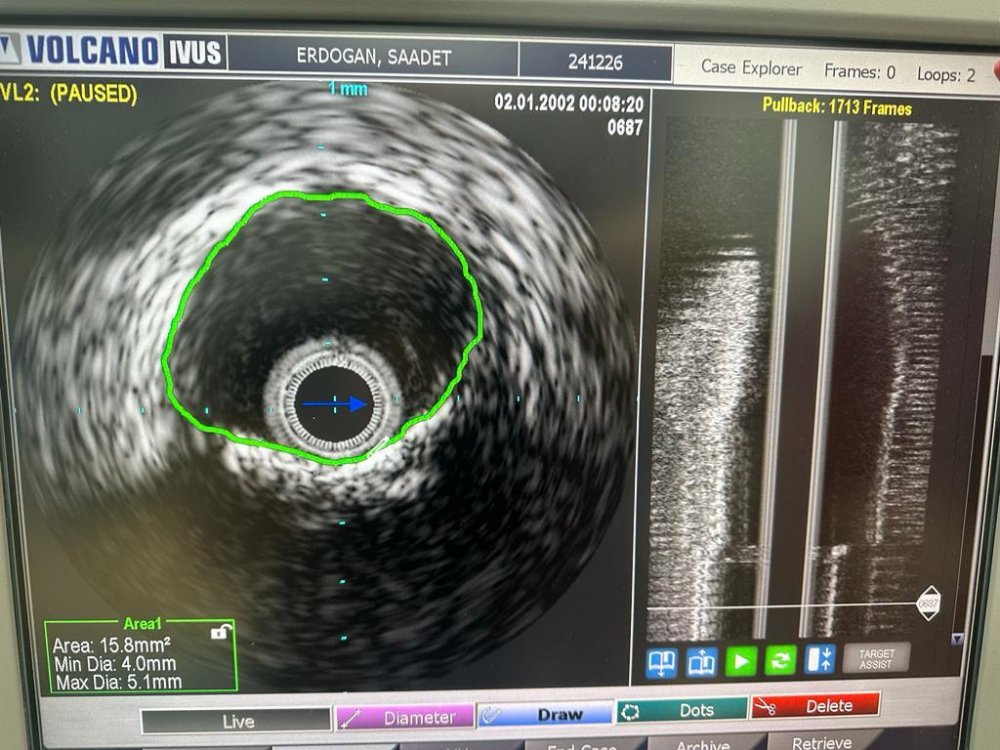

Kardiyoloji Uzm. Dr. Muzaffer Aslan tarafından yapılan açıklamada; “Bu Anjiografi işlemlerinin özelliği ise henüz ülkemizde yaygın olarak kullanılmayan ıvus denilen damar içi ultrason kullanılması ve kireçli damarlarda taş sertliğinde olan damar darlıklarını açmak için rotablatör kullanılmasıdır.

Ivus ile kalbin en önemli büyük olan ana damardaki görsel olarak darlık dediğimiz noktalarda damar sertliğinin gerçekten kritik darlığa neden olup olmadığı ya da damar plaklarının özelliklerini öğrenip buna göre stent kararı verilmektedir. Aksi durumda stent çapı küçük veya fazla olduğunda erken dönemde tekrar tıkanmalar meydana gelebilmektedir.